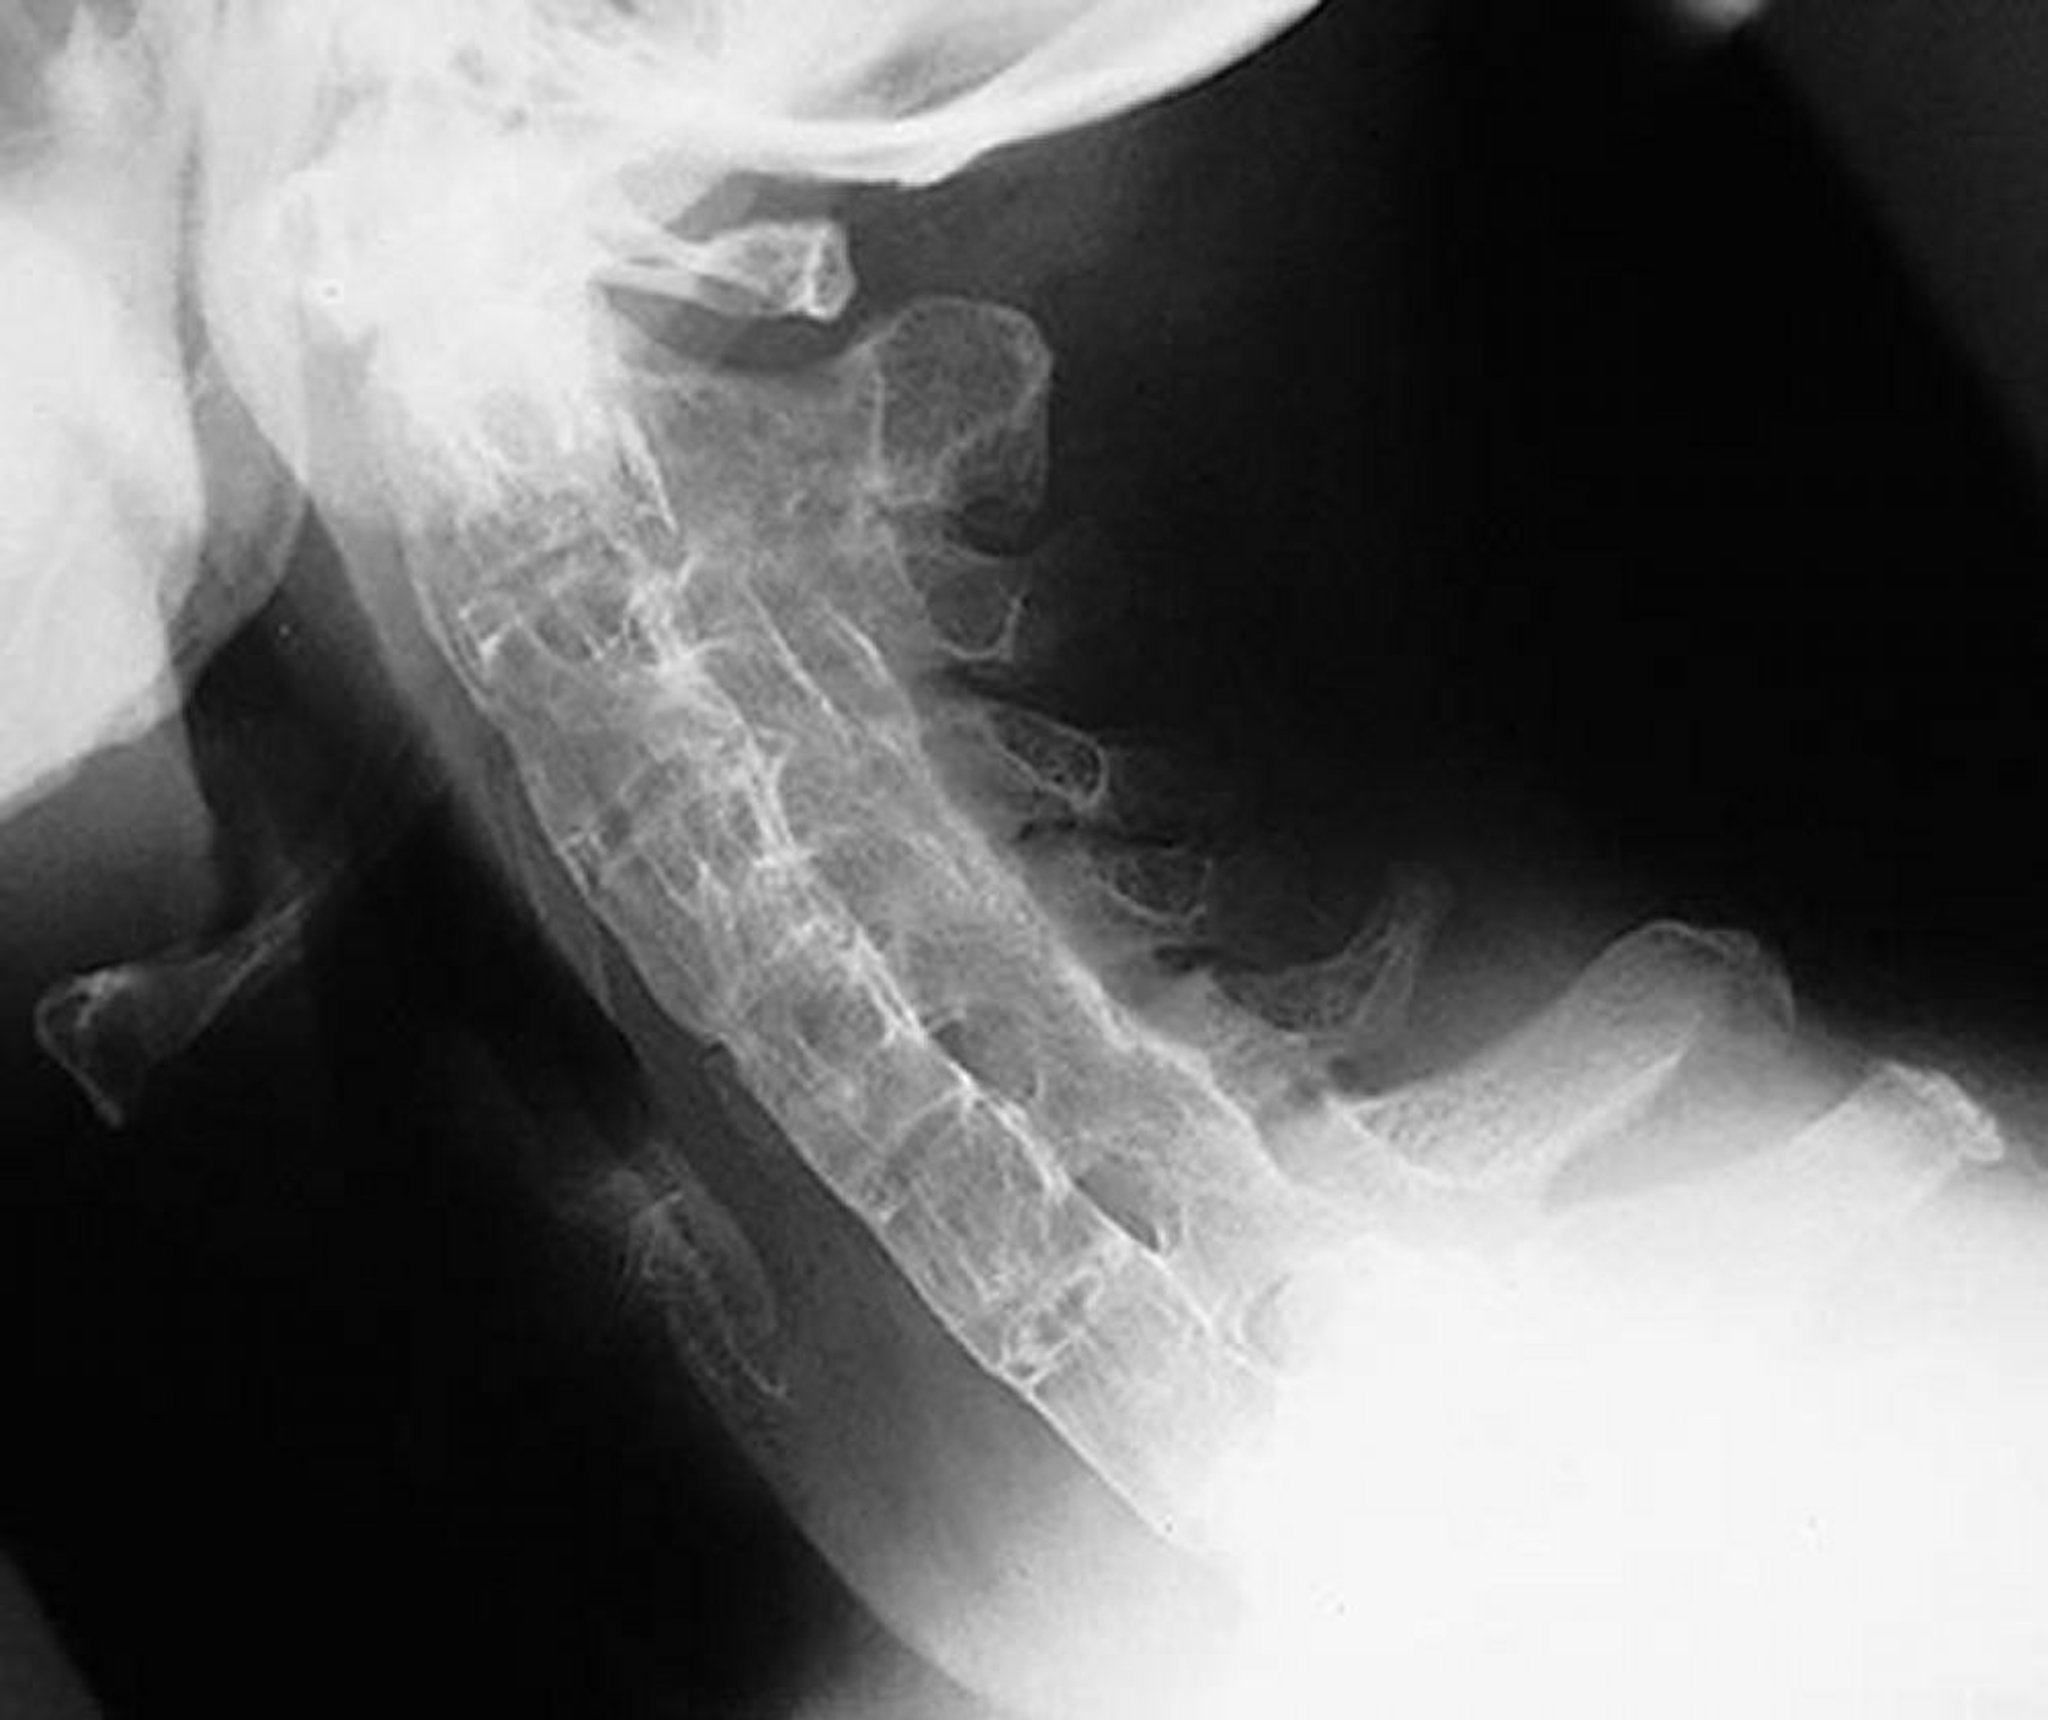

Colonna vertebrale a bambù nella spondilite anchilosante

Questa proiezione laterale della colonna cervicale mostra una colonna cervicale rigida in un paziente con spondilite anchilosante grave e di lunga data. La colonna vertebrale è completamente anchilosata ("colonna a canna di bambù") a causa dei sindesmofiti, della fusione delle faccette articolari (apofisarie) e delle calcificazioni legamentose paraspinali.